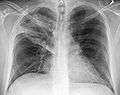

| A chest X-ray showing a very prominent wedge-shape bacterial pneumonia in the right lung. | |